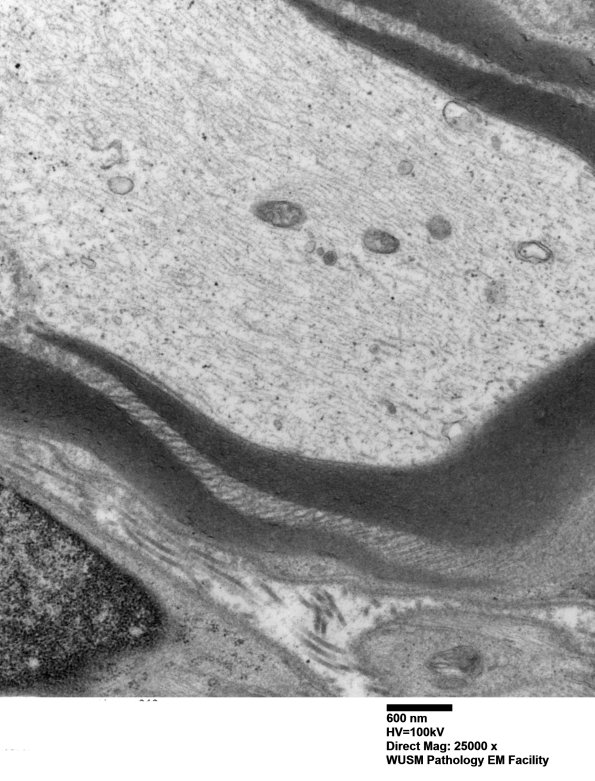

Higher magnification of image #8A2. (electron micrograph)